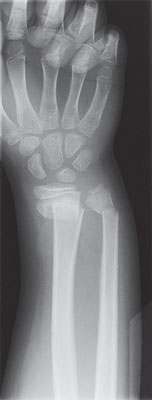

Bone X-ray

A bone X-ray is a way to take pictures of bones. It may also be called bone radiography. In this test, a low dose of radiation is passed through the body, producing digital images of the bones or images on a piece of film.

X-ray of a broken wrist |